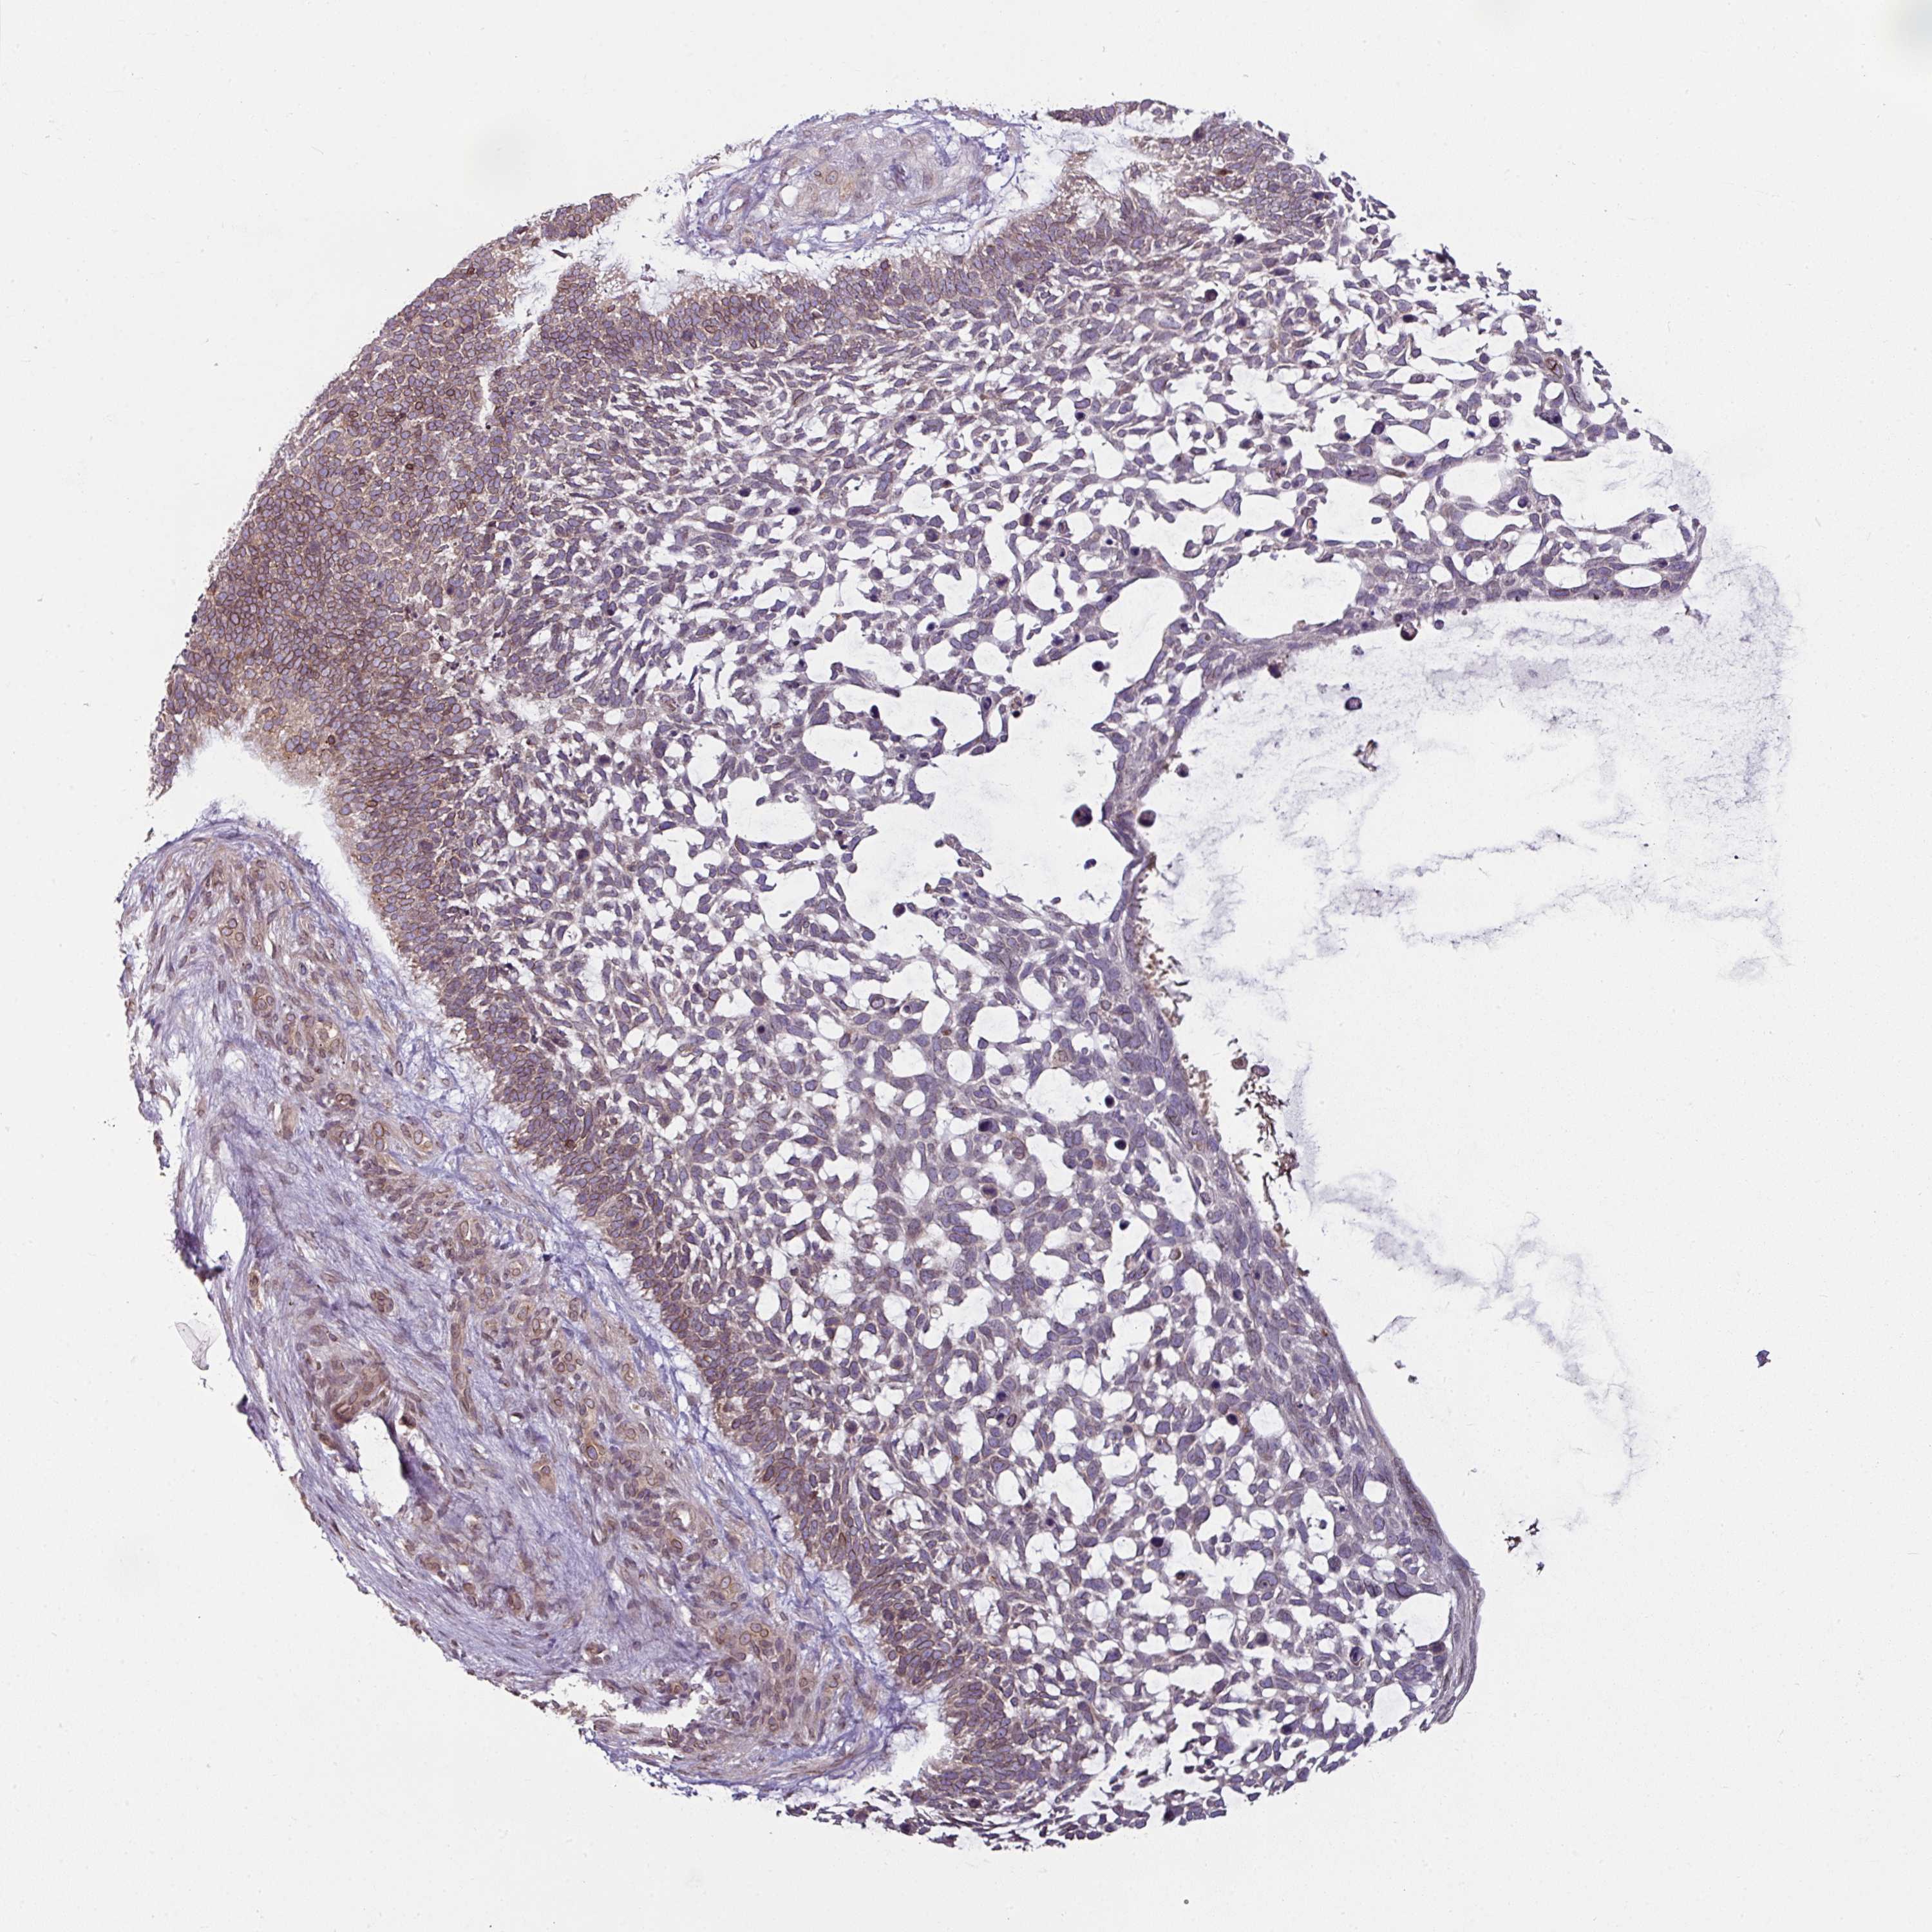

Basal cell and squamous cell cancer

SKIN CANCER - Protein expressioni

A mouse-over function shows sample information and annotation data. Click on an image to view it in a full screen mode. Samples can be filtered based on level of antibody staining by selecting one or several of the following categories: high, medium, low and not detected. The assay and annotation is described here.

Antibody stainingi

Antibody staining in the annotated cell types in the current human tissue is reported as not detected, low, medium, or high, based on conventional immunohistochemistry profiling in selected tissues. This score is based on the combination of the staining intensity and fraction of stained cells.

Each image is clickable and will lead to virtual microscopy that enables deeper exploration of all samples and also displays staining intensity scores, fraction scores and subcellular localization as well as patient and tissue information for each sample.

Antibody HPA050110

Antibody CAB004293

Squamous cell carcinoma, metastatic, NOS